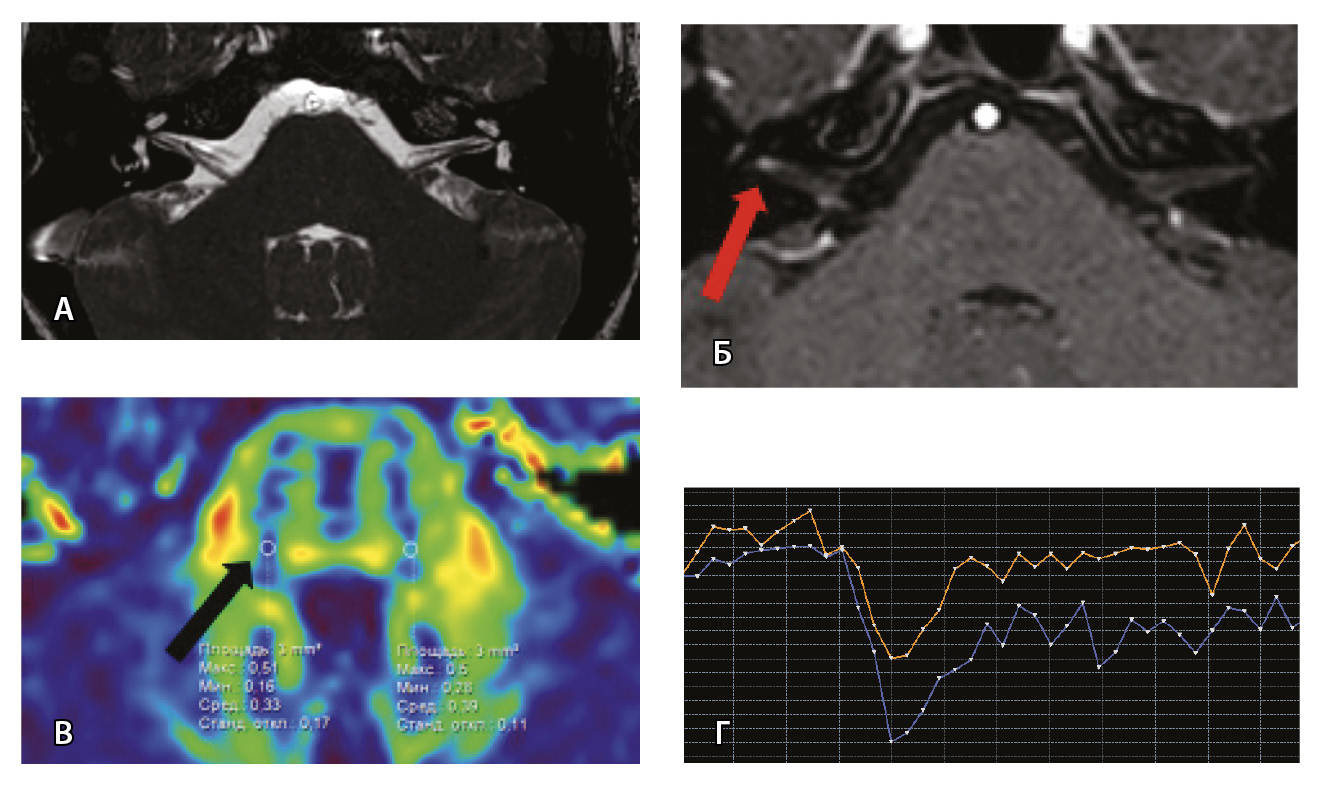

Рис. 3. Пациент Г. Магнитно-резонансная томография (МРТ) головного мозга: А – прицельная T2-SSFP на область мосто-мозжечкового угла; Б – Т1-взвешенное изображение с контрастным усилением; В – диффузионно-тензорная МРТ (фракционная анизотропия); Г – Т2*-перфузия (здесь и далее графики перфузии отражают зависимость повышения интенсивности МР-сигнала, то есть накопления контрастного вещества (вертикальная ось) от времени (горизонтальная ось), тем самым иллюстрируя основные показатели перфузии – relCBV, TTP, MTT). На изображениях T2-SSFP патологические изменения на уровне прохождения лицевых нервов во внутренних слуховых проходах (А), повышенное накопление вещества корешками лицевых нервов (Б) не определяются. Показатели фракционной анизотропии (В) и Т2*-перфузии (Г) на уровне моторных ядер лицевых нервов симметричны

Для наглядности представляем МП-МРТ ребенка без выявленных патологических изменений со стороны черепно-мозговых нервов согласно клиническим данным и при МП-МРТ (рис. 3) Исследование с контрастированием у ребенка без НЛН проводилось по другим показаниям для исключения острого демиелинизирующего процесса.